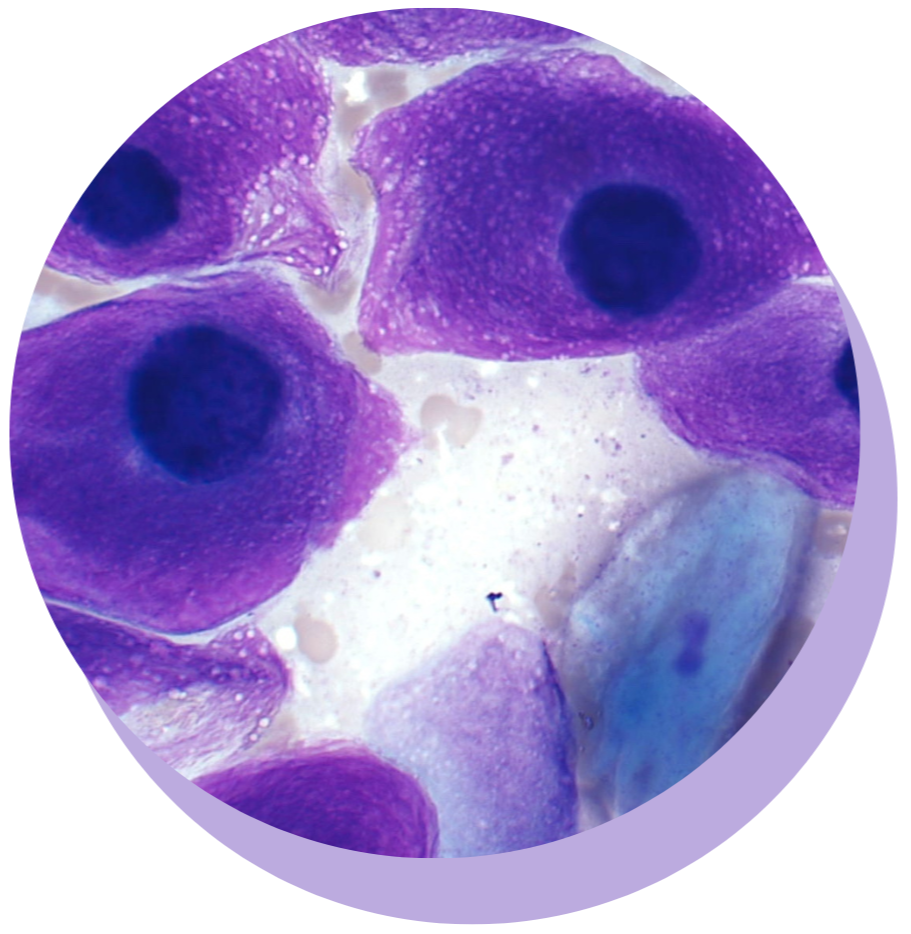

FREE WORKSHOP: CYTOLOGY 101

New to cytology? Watch our free 30 minute lesson and learn where to start.

Practical online courses in cytology and hematology for the veterinary professional, designed to catapult you from confused to confident.

MASTERING CYTOLOGY: SKIN AND SUBCUTIS

Boost your confidence and skills in interpretation of fine-needle aspirate (FNA) cytology from masses/lesions in the skin and subcutis.